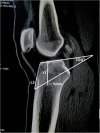

Methods: The measurements were performed on CT sagittal plane, including the thickness of cancellous bone (L1), the theoretical optimal angle of the tibial tunnel (TOA, which was measured between tibial plateau and the extension cord connecting the center of PCL insertion site with a point 5 mm superior from marrow cavity vertex), L2 - the distance from anterior tunnel aperture to anterior end of tibial plateau, L3 - the distance from anterior tunnel aperture to tibial tuberosity (lowest edge of patellar ligament attachment).

Results: The value of TOA and L3 were 35.4 ± 7.9 ° and 26.8 ± 11.4 mm, respectively. L1 and L2 were higher in males than females (L1, P = 0.002; L2, P = 0.046). Regarding age, L1, TOA, L2 and L3 were higher in the 46-60 years group than 31-45 years group (P = 0.02, P = 0.001, P = 0.038, P = 0.032, respectively). With regard to height, L1 was lower in group I - < 1.66 m than group II - 1.66 to 1.75 m and group III - > 1.75 m (I v II, P = 0.015, I v III, P = 0.026). L2 was also lower in group I than group II and group III (I v II, P = 0.026, I v III, P = 0.006). TOA and L3 showed no significant differences among sex and height groups (P > 0.05).

Conclusions: TOA (35.4 ° ± 7.9 °) and L3 (26.8 ± 11.4 mm) could be used as a reference for ideal tibial tunnel placement in transtibial anatomic PCL reconstruction, so as to prevent recurrent PCL laxity and ensure good graft healing. However, further clinical validation is needed.